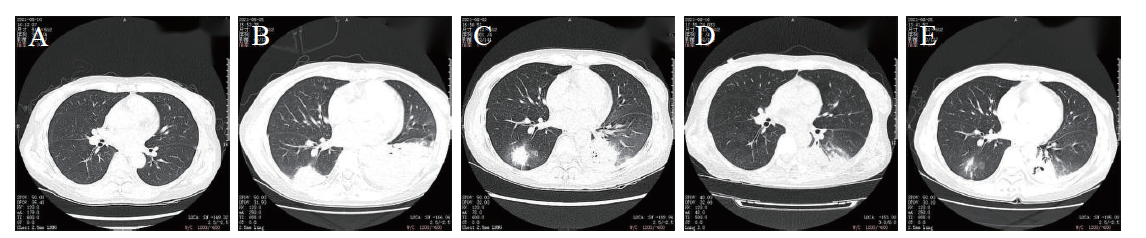

确诊后立即调整抗生素为左氧氟沙星针(0.5 g、1次/日)+替加环素(50 mg、1次/12 h)。6月2日复查胸部CT:双肺渗出性、实变性病灶较前吸收,但患者仍有发热,体温37.6~38.4℃。6月4日调整抗生素,停用替加环素,改用阿奇霉素针(0.5 g、1次/日),6月5日起患者体温逐渐下降,6月6日体温恢复正常,呼吸道症状改善。6月16日复查胸部CT:右下肺病灶吸收明显,6月18日复查血红蛋白69 g/L,白细胞2.0×109 /L,中性粒细胞绝对值1.40×109 /L,血小板178×109 /L,超敏CRP 34.8 mg/L,6月25日复查胸部CT:左下肺实变病灶进一步吸收,见图23。患者症状稳定,疗效评估为好转,予以出院。

图2 一例淋巴瘤化学治疗后免疫抑制并发嗜肺军团病患者住院期间胸部CT影像学改变

注:A为5月11日胸部CT,双肺未见渗出性病灶;B为5月25日胸部CT,双下肺见大片状密度增高影;C为6月2日胸部CT,提示双下肺感染性病灶,左侧少量胸腔积液,较前吸收;D为6月16日胸部CT,提示双肺感染性病灶,左侧少量胸腔积液,较前吸收;E为6月25日胸部CT,提示双肺感染性病灶,较前略有吸收。